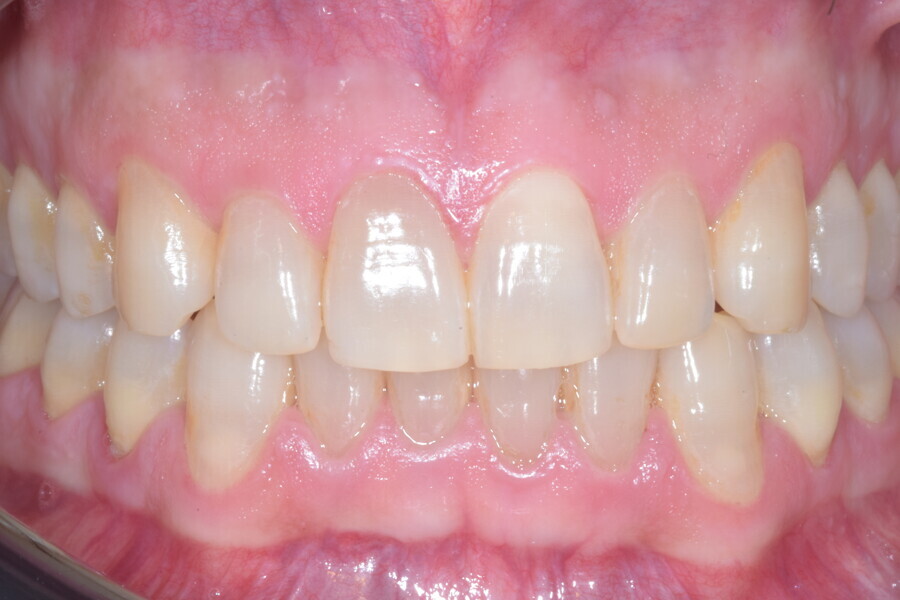

Fig. 13

Fig. 14

Fig. 15

Fig. 16

Fig. 17

Fig. 18

A 37-year-old male patient presented with the chief need for re establishing anterior alignment in both arches. Facial analysis showed a short face with a flat profile but proper chin projection (Figs. 9–12), and clinical examination revealed a skeletal Class I (ANB = 0.89°) and dental Class I malocclusion with severe deep bite (almost 100%), a deep curve of Spee, normal maxillary central incisor torque (Ui–FH = 110°), mild maxillary crowding and moderate mandibular crowding (Figs. 13–18). The deep bite components were represented in this patient by the severe skeletal condition of hypo divergent pattern (FMA = 14.24°) with normal maxillary and mandibular incisor inclination and decreased gonial angle (110.46°). Analysis of the cephalometric radiograph indicated a reduced lower anterior facial height, combined with a hypo-divergent pattern (Fig. 19). The only treatment option suggested was orthodontic treatment with aligners for deep bite correction with all the features described (bite ramps, pressure area, 3D curve of Spee levelling, Class II elastics and heavy occlusal contacts).